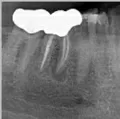

Здравствуйте! Есть ли у меня киста? Если да, то как срочно нужно делать операцию и как она называется?

Какой зуб вы имеете ввиду? Уточните. 18 и 48 зуб необходимо удалить. Далее расскажу после уточнения.